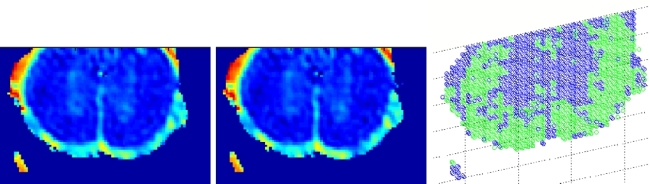

Figure 2: (Left and center) Deformation at scale 4 and 2. (Right) Final deformation.

We aim to develop algorithms for separating a DT image into multiple regions. A region could be an actual anatomical structure, such as the corpus callosum in a brain image. Alternatively, a region could be a collection of fibers that have the same or similar function. In either case, the problem is to cluster a collection of tensors or fibers into groups according to some measure of similarity. We are studying metrics on diffusion tensors and fibers that are not only mathematically grounded but also biologically meaningful. Using these metrics, we are developing nonlinear dimensionality reduction techniques that will transform the DT data into a collection of clusters in a Euclidean space. The low-dimensional representation of the original DT data is then be segmented using standard clustering techniques. Figure 3 shows the results of our algorithm on segmenting the white and grey matter in the spinal cord.

Figure 3: (Left and center) apparent diffusion coefficient images for two slices of the spinal cord. (Right) fiber clustering results.